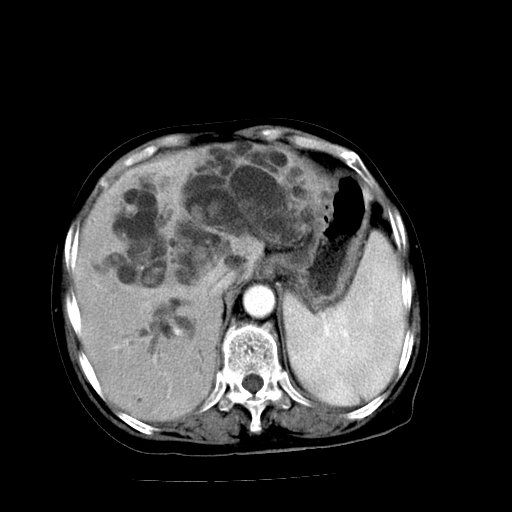

以下是引用卜一在2009-4-7 5:06:00的发言:[br]左右肝内胆管结石伴扩张合并胆系感染;不除外胆管细胞癌可能。支持! [br] [br]

以下是引用随光逐影在2009-4-7 8:21:00的发言:[br]肝内外胆管多发性结石并肝内外胆管扩张;胆系感染。